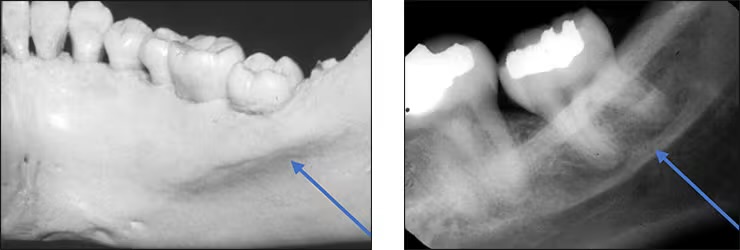

Submandibular gland fossa

Depression in the bone on the lingual aspect of the posterior mandible.

Bilateral below the maternal oblique ridge/mylohyoid line.

Is where the submandibular salivary gland rests.

Typically appears radiolucent